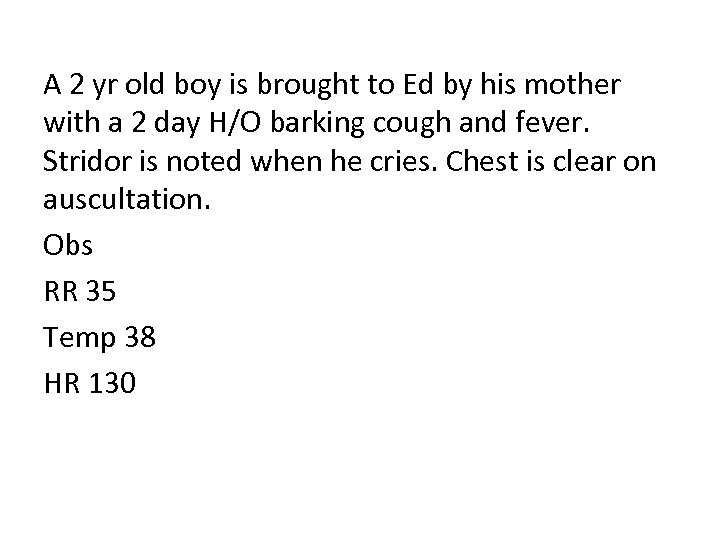

A 2 yr old boy is brought to Ed by his mother with a 2 day H/O barking cough and fever. Stridor is noted when he cries. Chest is clear on auscultation. Obs RR 35 Temp 38 HR 130

Q 1. What is the most likely clinical diagnosis? (1 mark) Q 2. Give 2 of the five components of the score that can be used to assist in the assessment of the severity of this condition. (2 marks)

Q 1. What is the most likely clinical diagnosis? (1 mark) Croup or viral laryngotracheobronchitis Q 2. Give 2 of the five components of the score that can be used to assist in the assessment of the severity of this condition. (2 marks) • • • Presence of stridor Level of consciousness / alertness Degree of air entry Presence of Cyanosis Retractions / Recession